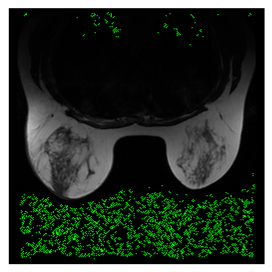

4.3. The Results

In this subsection, we describe three experiments used to measure the performance of the proposed method. The first experiment shows the stegoimage and marks the pixels’ positions that have been modified during the embedding process, as shown in Table 2, Table 3, Table 4, Table 5, Table 6 and Table 7. To make modified pixel positions have a pronounced effect, we set bpp (bit per pixel) rate at 0.05 and 0.025. It can be seen from the results that the proposed local complexity function can distinguish ROI and RONI from most of the medical images, so modified pixels are mainly gathered in RONI. However, it is observed that the proposed local complexity function cannot distinguish between ROI and RONI in the Prostate-MRI database due to the relative complexity of the image. Besides, “Modified BPP” represents the proportion of pixels in the image that have been modified. We observed that the performance of “baboon” in the grayscale standard images database is poor because that image’s pixels are relatively complex. It becomes challenging to select the more embeddable pixels based on the proposed local complexity function. Nevertheless, the modified pixel positions in other grayscale standard images, such as Lena and Barbara, are relatively smooth, verifying that our local complexity function is also applicable to general images.